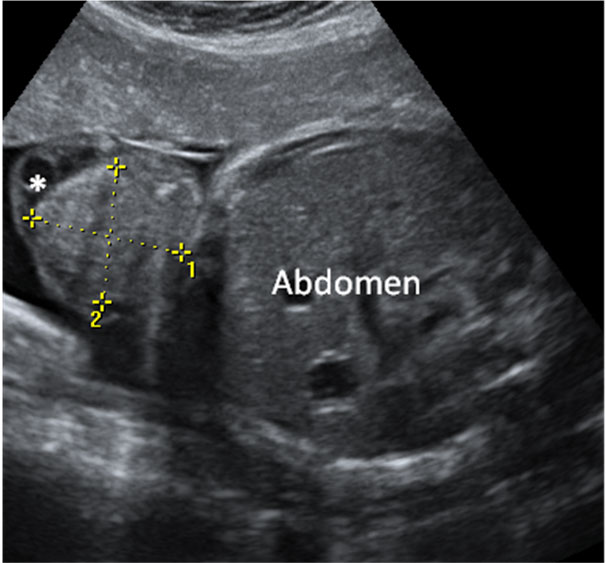

En la ecografía podemos ver una hernia intestinal (u onfalocele), lo que significa que parte del intestino del feto está fuera del abdomen. Observamos la sección transversal del abdomen fetal. A la izquierda, contenido intestinal (entre marcas de medición) herniado fuera del abdomen, debido a un defecto en la inserción del cordón umbilical, que se marca en la imagen con una estrella (*).

Onfalocele o intestino del feto fuera del abdomen